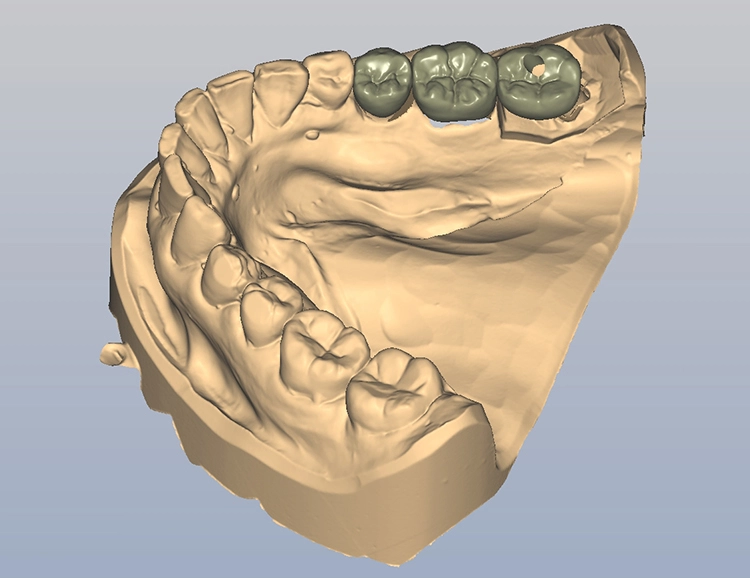

Bilder: Dr. Lampson / HannkerNach dem Ausgießen der Abformung sowie dem Scan des Gips- und Antagonistenmodells (Abb. 11a bis d) folgten das Kronendesign und die Fräsparametereinstellung per CAD/CAM-Programm (PowerMill Pro, Autodesk) (Abb. 12). Hergestellt wurden die Kronen aus Lithium-Disilikat-CAD/CAM-Blöcken (InitialTM LiSi Block, Farbe A2) (Abb. 13), die sich insbesondere durch eine hohe Opaleszenz bei hochtransluzenten (HT) Farbtönen auszeichnen und so auch ohne weitere Charakterisierung hochästhetische Ergebnisse erzielen.

Bilder: Dr. Lampson / HannkerNach 35-minütigem Schleifen (Exocad PowerMill CAM, DMG) wurde die Restauration aus dem Block entfernt und der Bereich der Anstiftung geglättet. Anschließend galt es, die Kronen auf den jeweiligen Formen und am Modell zu prüfen, wobei sich bereits eine perfekte Randpassung zeigte (Abb. 14 und 15). Danach erfolgte die Glaslötung der Implantatkrone auf das individuell angepasste Zirkonoxid-Abutment (Abb. 16).